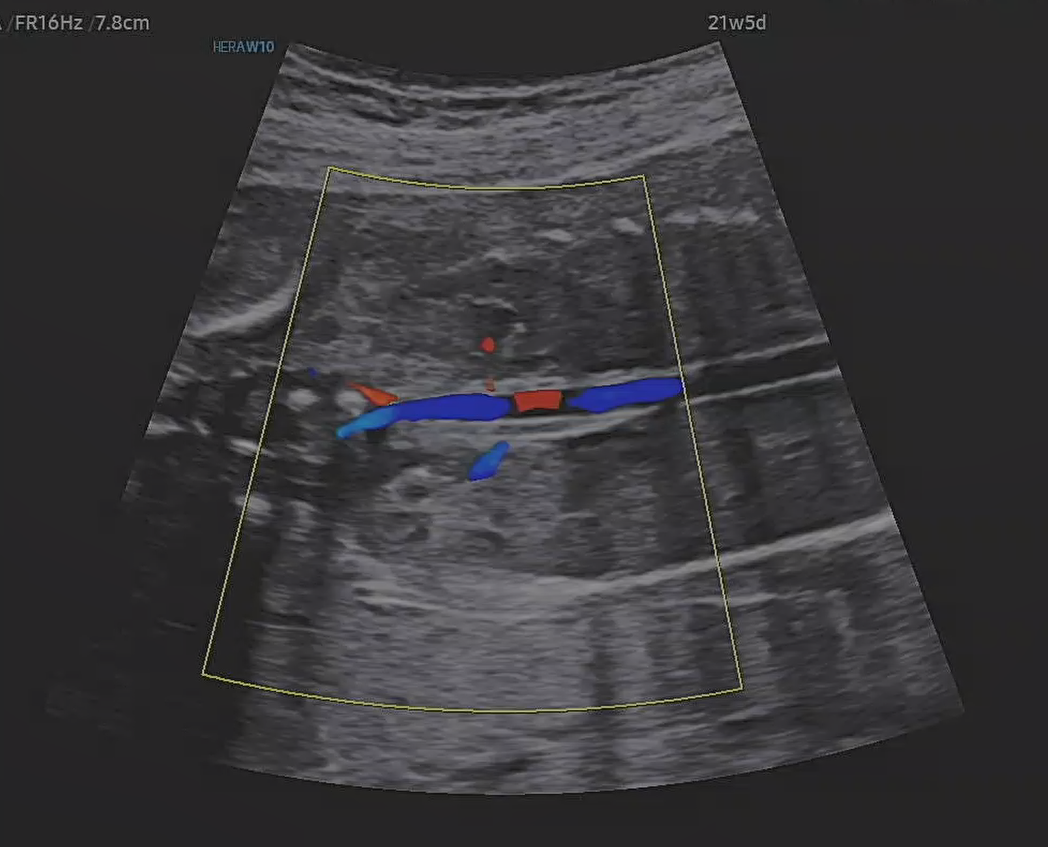

신장?으로 들어가는 혈류라고 하셨던것 같다.

이런것까지 보이는게 정말 신기했다.

초음파 진단 기술이 정말 많이 발전 한것 같았다.

어떻게 태아 혈류까지 이렇게 잘 보이는지 원